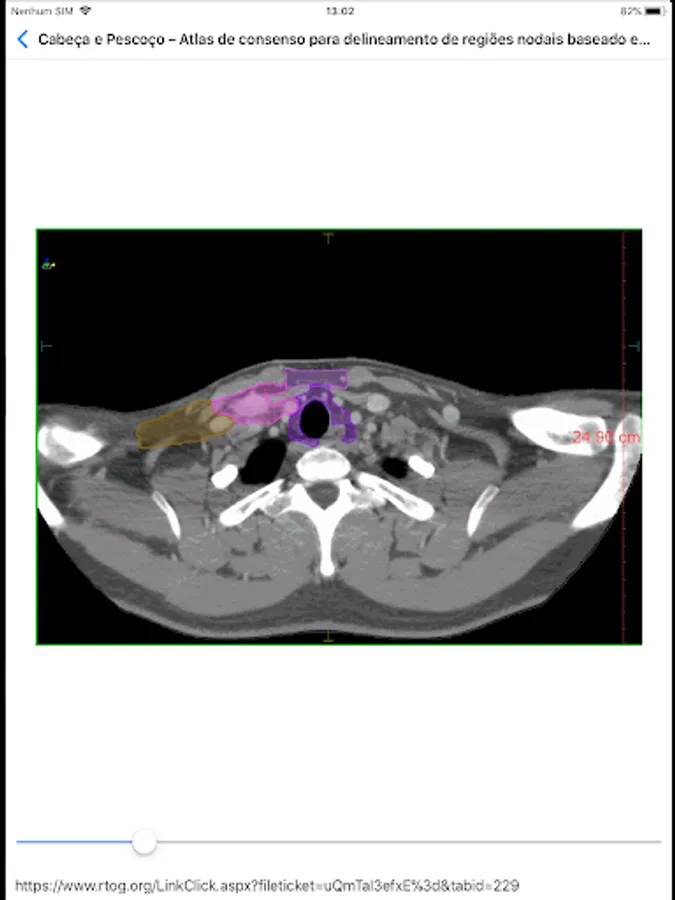

Radio ICESP Screenshots